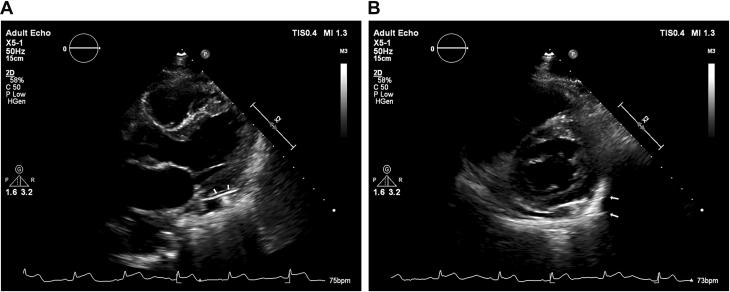

Echocardiography resolved the ambiguity about the location of the bullet. The transthoracic echocardiogram showed the bullet lodged inside the pericardium along the inferolateral aspect of the left ventricle, with clear separation from the epicardium. There was mild pericardial effusion (Figures 5A and 5B, Video 1). Transesophageal echocardiography also confirmed the intrapericardial location of the bullet.

Figure 5.

Echocardiographic Views

(A) 2-dimensional transthoracic echocardiogram showing the bullet (arrows) inside the pericardium as 2 parallel shadows along the inferolateral aspect of the left ventricle. ST-segment elevation can also be noted in the accompanying electrocardiogram trace. (B) The 2-dimensional transthoracic echocardiography in the parasternal short-axis view showing the intrapericardial bullet as 2 parallel shadows (arrows). Mild pericardial effusion is also noted.